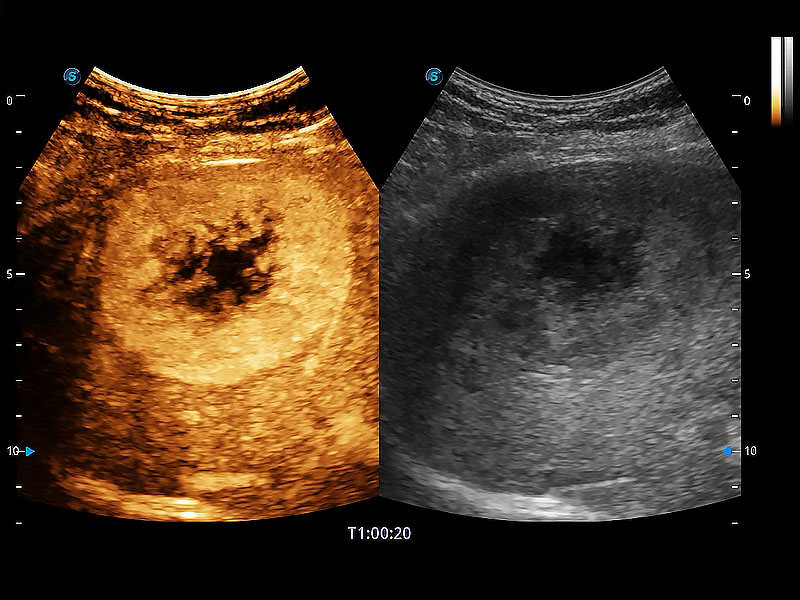

极大提升超低速微细血流的检出能力,同时更精准地滤除软组织和超声信号,为兽用医生提供以往无法通过常规血流获得的疾病诊断信息。

在传统二维血流成像的基础上,呈现血流的立体感,具有动感的生命力之美。即便是微小的血管也能轻松应对,提高了血流的视觉敏感性。